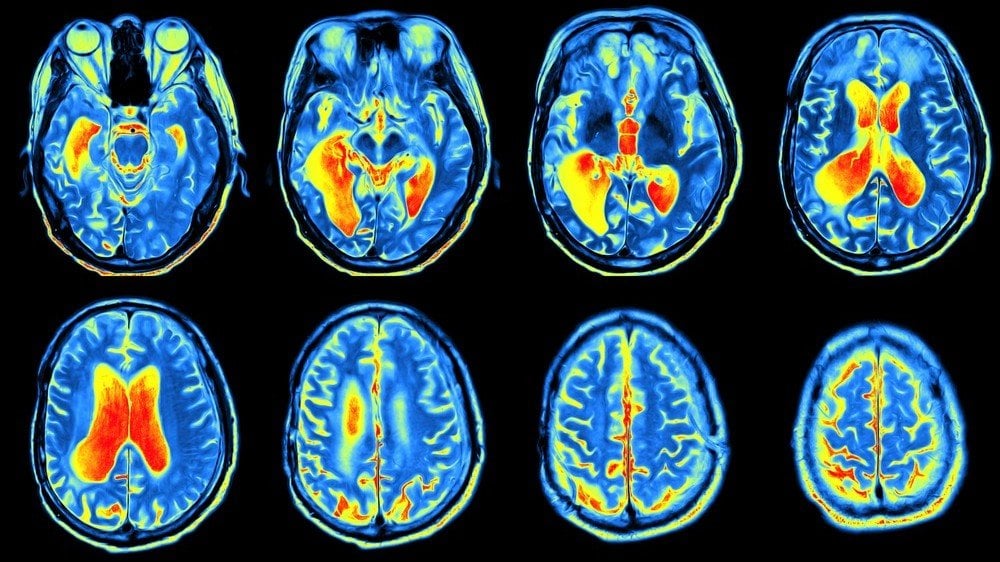

Beyin ve Merkezi Sinir Sistemi Hastalıkları

Glikoz, beynin en temel yakıtıdır. PET taramaları için hazırlanan ilaçlardaki izleyiciler, glikoz ve benzeri bileşiklere tutturulur. Bu şekilde tarayıcı, radyoaktif glikozu görüntüleyerek beynin en fazla oranda glikoz kullandığı bölgeleri tespit eder.

PET taramasının teşhis ve tedavisinde kullanıldığı bazı merkezi sinir sistemi hastalıkları şunlardır:

- Beyin tümörleri

- Alzheimer hastalığı

- Epilepsi

- Parkinson hastalığı

- Depresyon

- Kafa travması